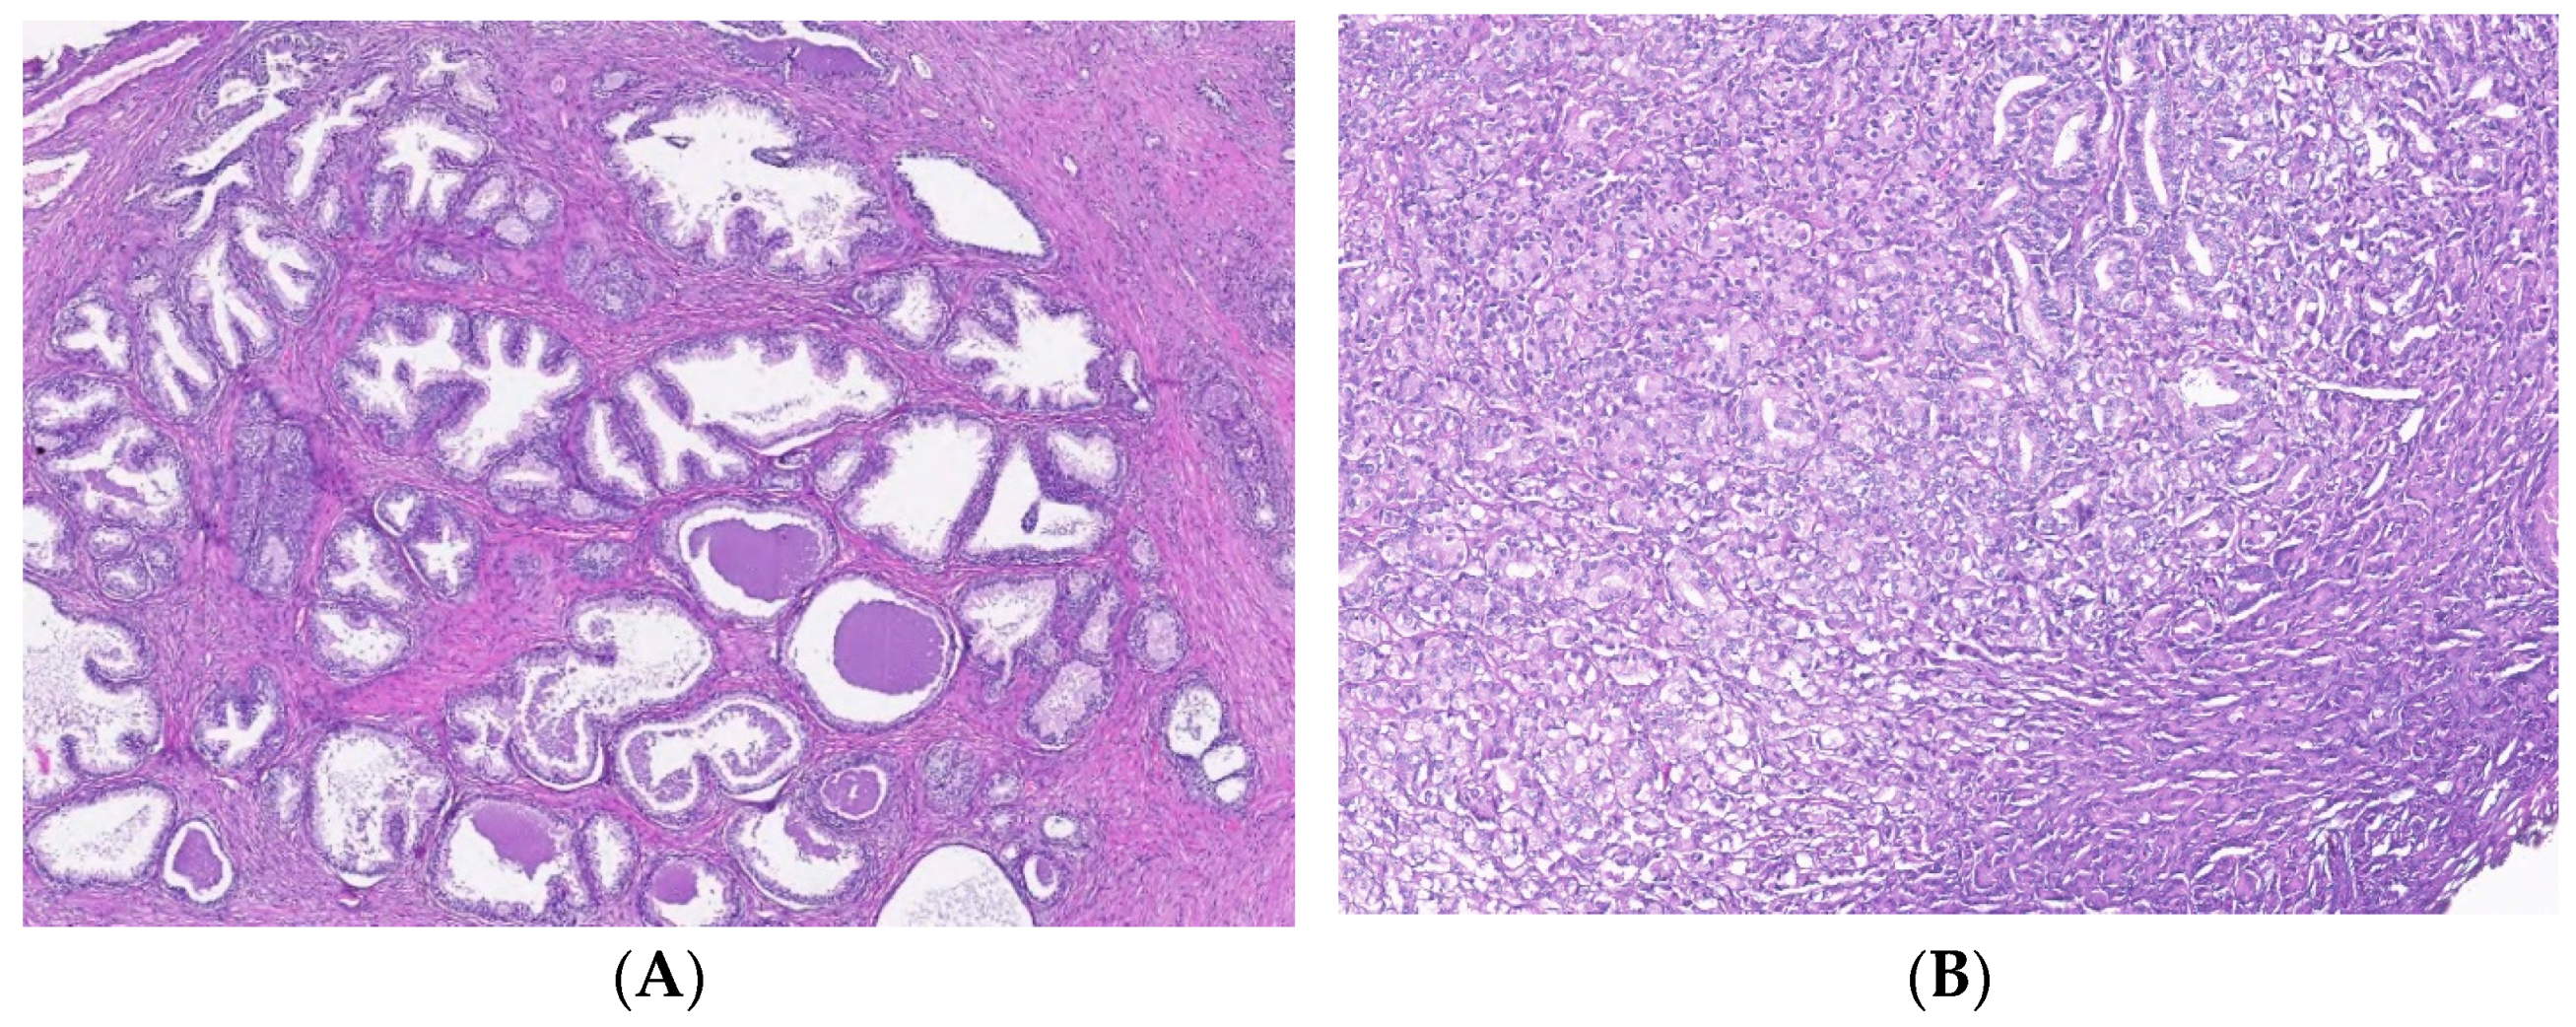

2.2. Morphological Evaluation of Tissue Samples